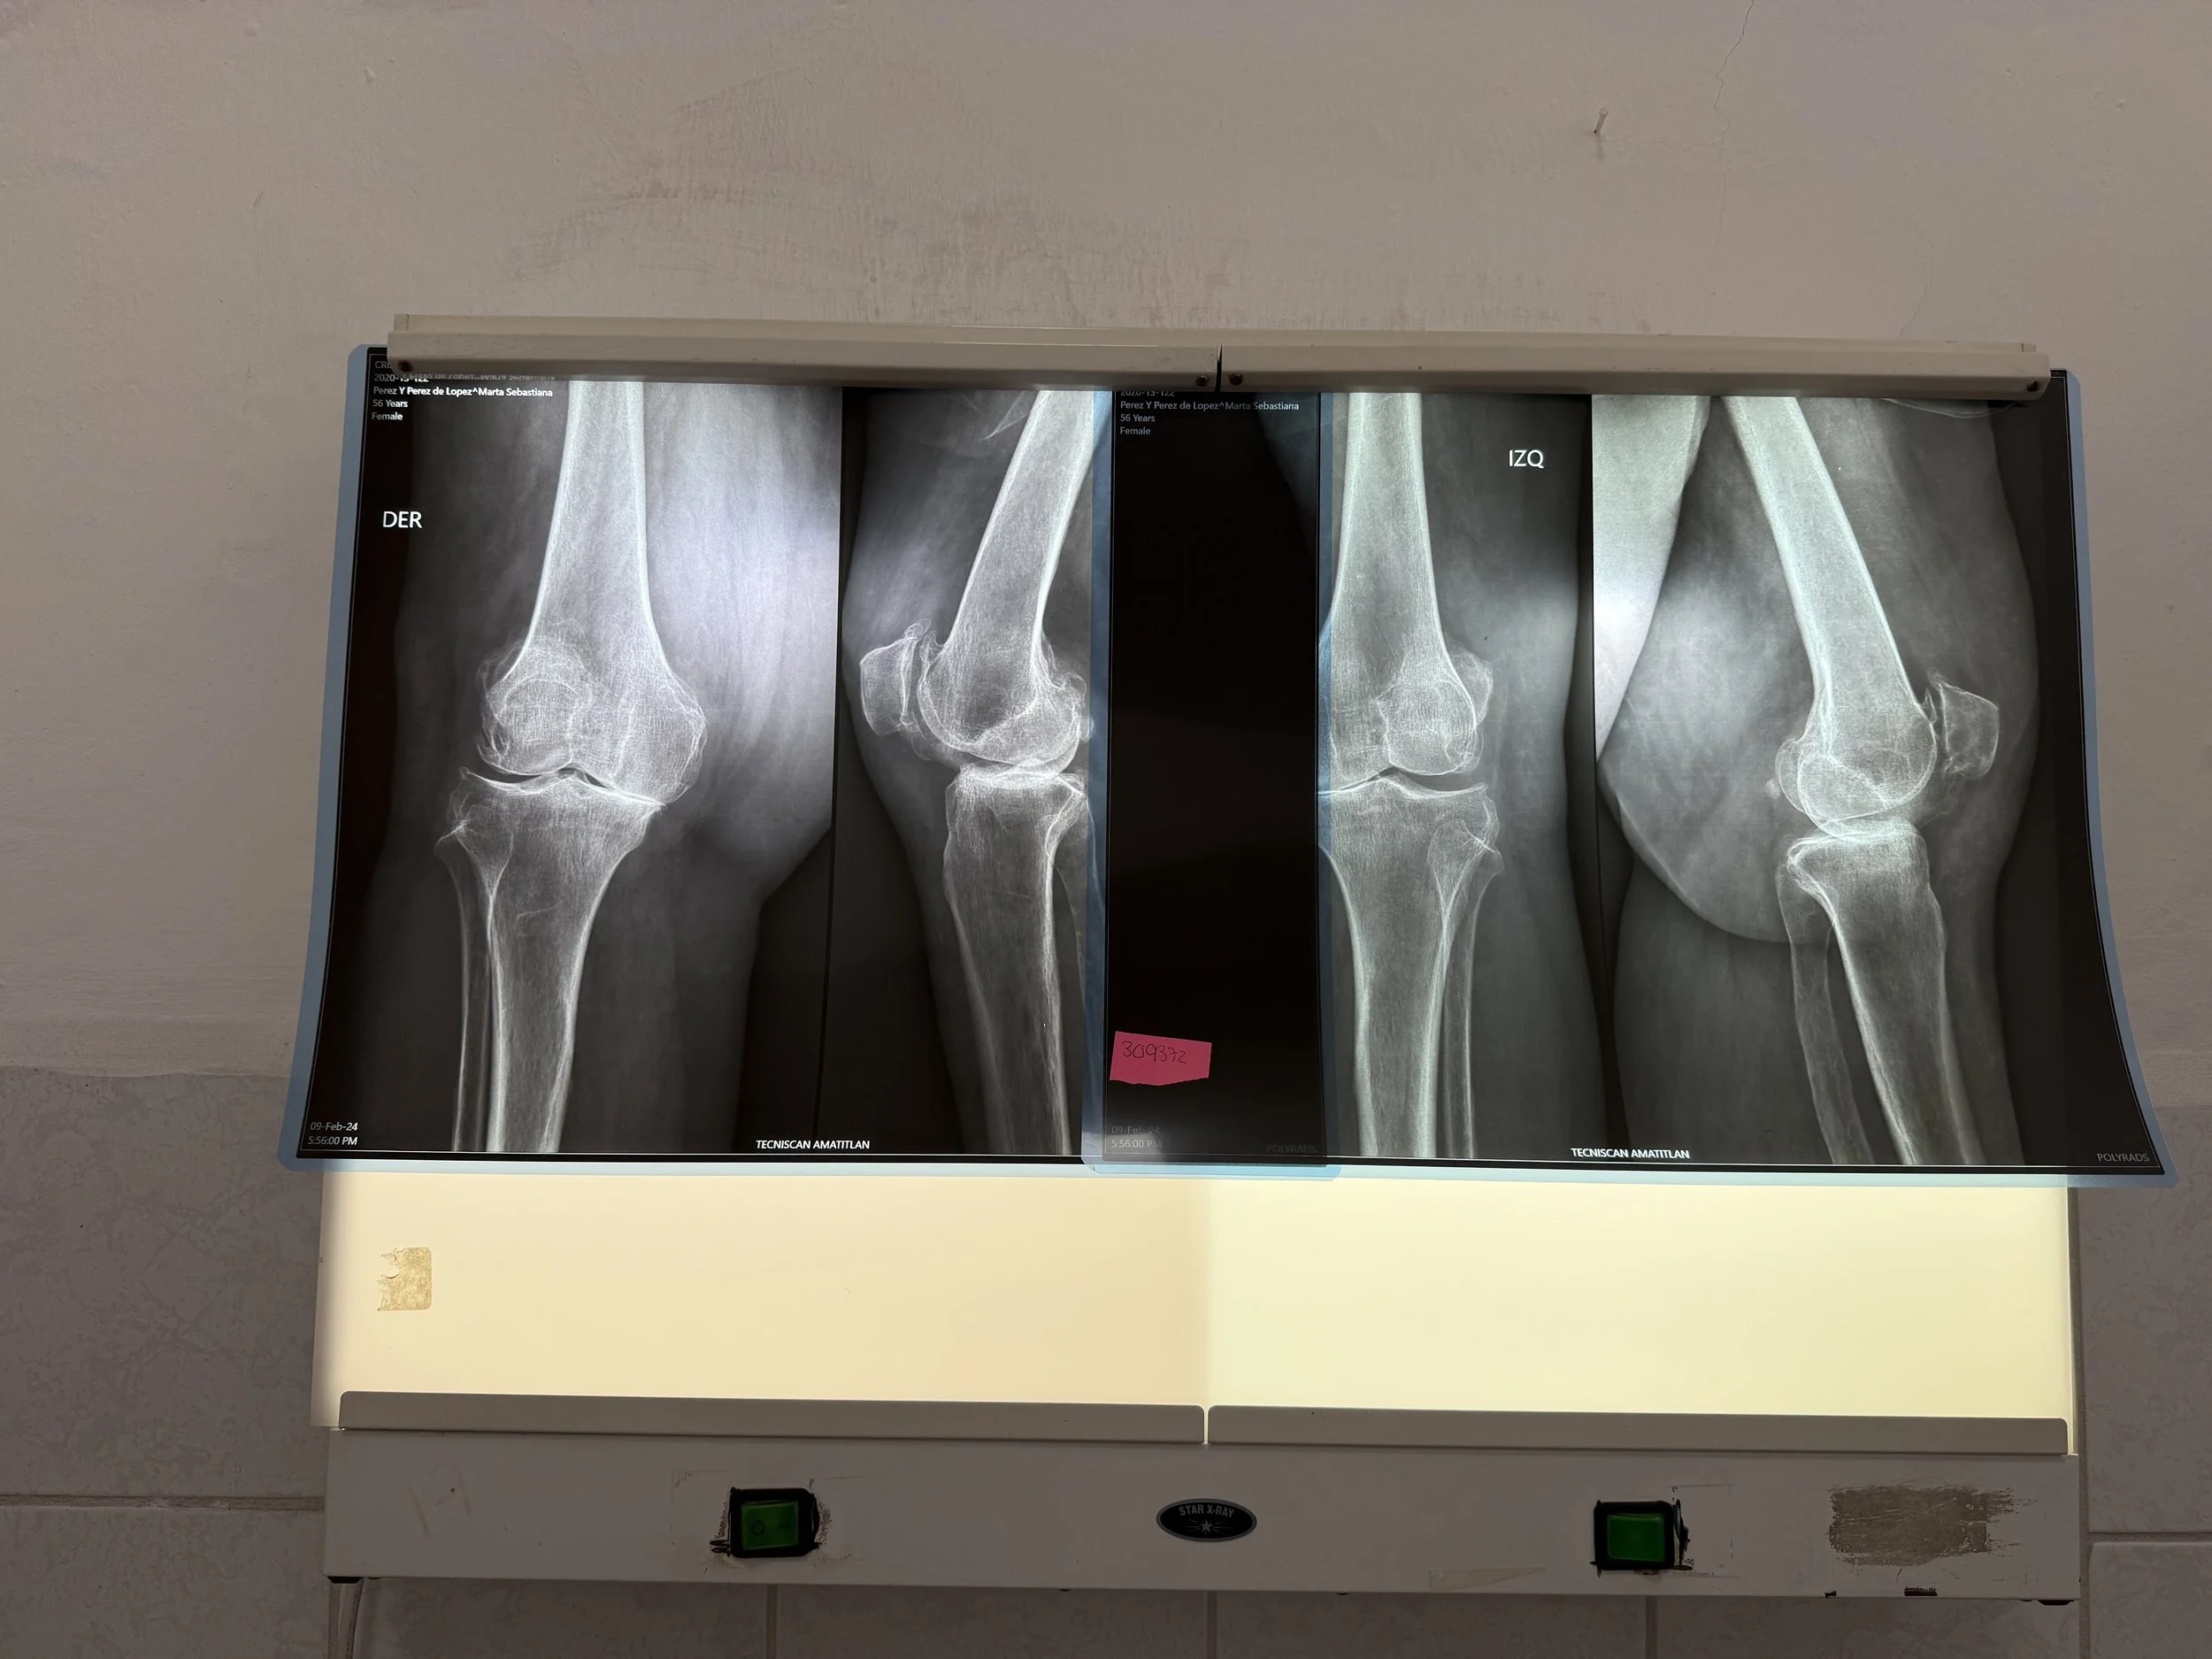

Today, we had the humble privilege of seeing over 100 patients in need of surgical care for hip, knee, foot, and ankle deformity. We will begin tomorrow with 6 operating rooms, 25 cases planned, 9 surgeons, 7 anesthesiologists, and 43 health care professionals working together.